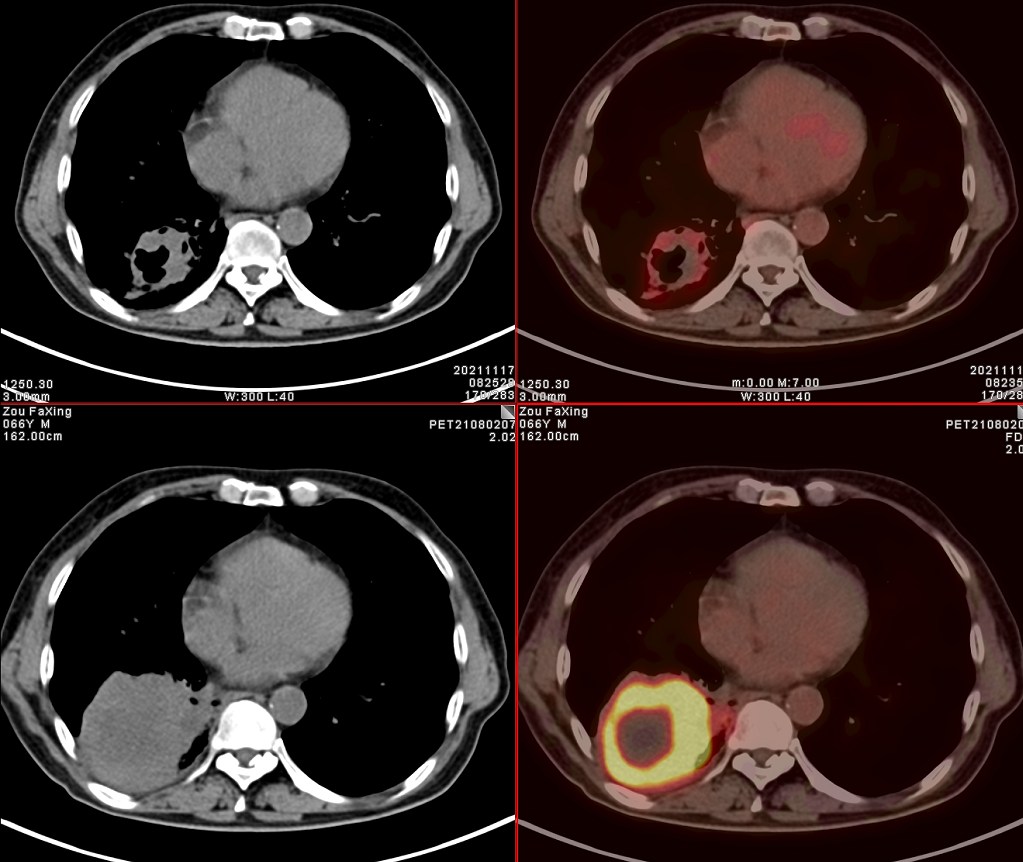

依据影像学分期,该患者后续进行了综合治疗:免疫+化疗+靶向治疗,其中化疗3期,免疫治疗2期及靶向治疗。3个月后患者再次进行了PET/CT检查,对治疗效果进行了评估。2021年11月PET/CT检查结果:

肿瘤病灶明显缩小、实性成分明显减少,肿瘤FDG代谢明显减低,相邻胸膜浸润明显改善,已经没有胸水征象。另外,全身其他部位未见明确转移性病变。

上面两张为治疗后,下面为治疗前

复查后PET/CT诊断:右肺下肺癌综合治疗后,肿瘤病灶明显缩小,FDG代谢明显减低,相邻胸膜未见高代谢病变,考虑肿瘤治疗后疗效显著,仅少量肿瘤活性残留。

根据我们PET/CT诊断,患者第二天就进行残余右肺癌病灶的手术切除。通过上述综合治疗,将一个原本没有手术机会的患者从死神的手中抢回来。虽然愈后情况有待进一步观察,但是通过PET/CT评价,患者病情明显好转,身体素质明显好转,生活质量明显提高,将不可能变为可能。后续进一步疗效,我会密切关注,后期随访再和大家分享。